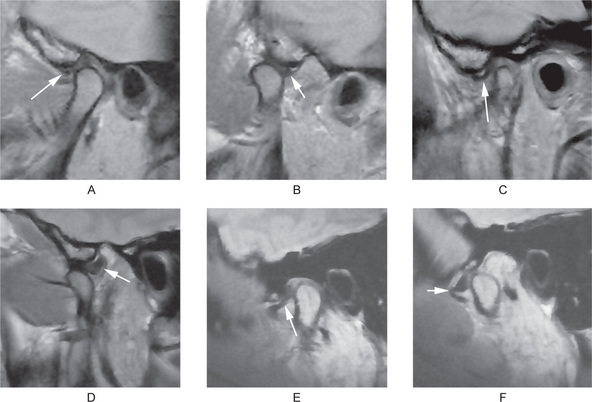

Figure 17-41 Magnetic resonance imaging of the temporomandibular joints.

(A, B) From the same patient, in closed (A) and open (B) mouth position. (A and B) show Normal disk relationship with the condylar head and articular fossa/eminence. (C, D) From the same patient, in closed (C) and open (D) mouth position. (C, D) show disc displacement with reduction (DDWR). (E, F) From the same patient, in closed (E) and open (F) mouth position. (E and F) show disc displacement without reduction. (DDWOR) The arrows point to the articular discs.